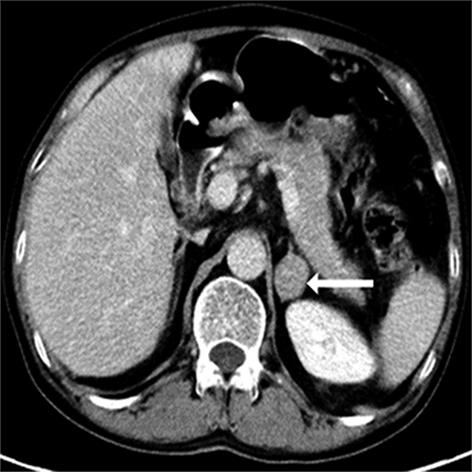

• 嗜铬细胞瘤及副神经节瘤不同生化表型的CT征象对比研究

2024, 49(2):203-209. DOI: 10.13406/j.cnki.cyxb.003433

摘要 (51) HTML (33) PDF 3.10 M (96) 评论 (0) 收藏

摘要:目的 分析生化阴性嗜铬细胞瘤及副神经节瘤(pheochromocytomas and paragangliomas,PPGLs)的电子计算机断层扫描(computed tomography,CT)征象是否有别于生化阳性PPGLs,同时了解生化阳性PPGLs不同表型的CT征象是否存在差异。方法 回顾性分析131例PPGLs患者的术前腹部增强CT图像,包括肿瘤位置、大小、形态、囊变坏死、液-液分层、钙化、向心结节状强化、肿瘤内粗大血管、强化包膜、绝对廓清率及相对廓清率。根据生化水平,将患者分为生化阳性组和阴性组,阳性组进一步分为去甲肾上腺素型、肾上腺素型及多巴胺型。比较各组及各表型间的CT征象差异。结果 相较于生化阴性组,阳性组PPGLs更大(Z=-2.064,P=0.039)、囊变坏死(χ2=6.610,P=0.010)及向心结节状强化(χ2=3.909,P=0.048)的比例更高;相较于去甲肾上腺素型,肾上腺素型PPGLs更大(Z=-2.036,P=0.042)、强化包膜比例更高(χ2=7.242,P=0.007)。结论 肿瘤大小、囊变坏死及向心结节状强化的CT征象有助于术前诊断生化阴性PPGLs,肿瘤大小及强化包膜有助于解释去甲肾上腺素型及肾上腺素型PPGLs不同临床表现产生的机制。